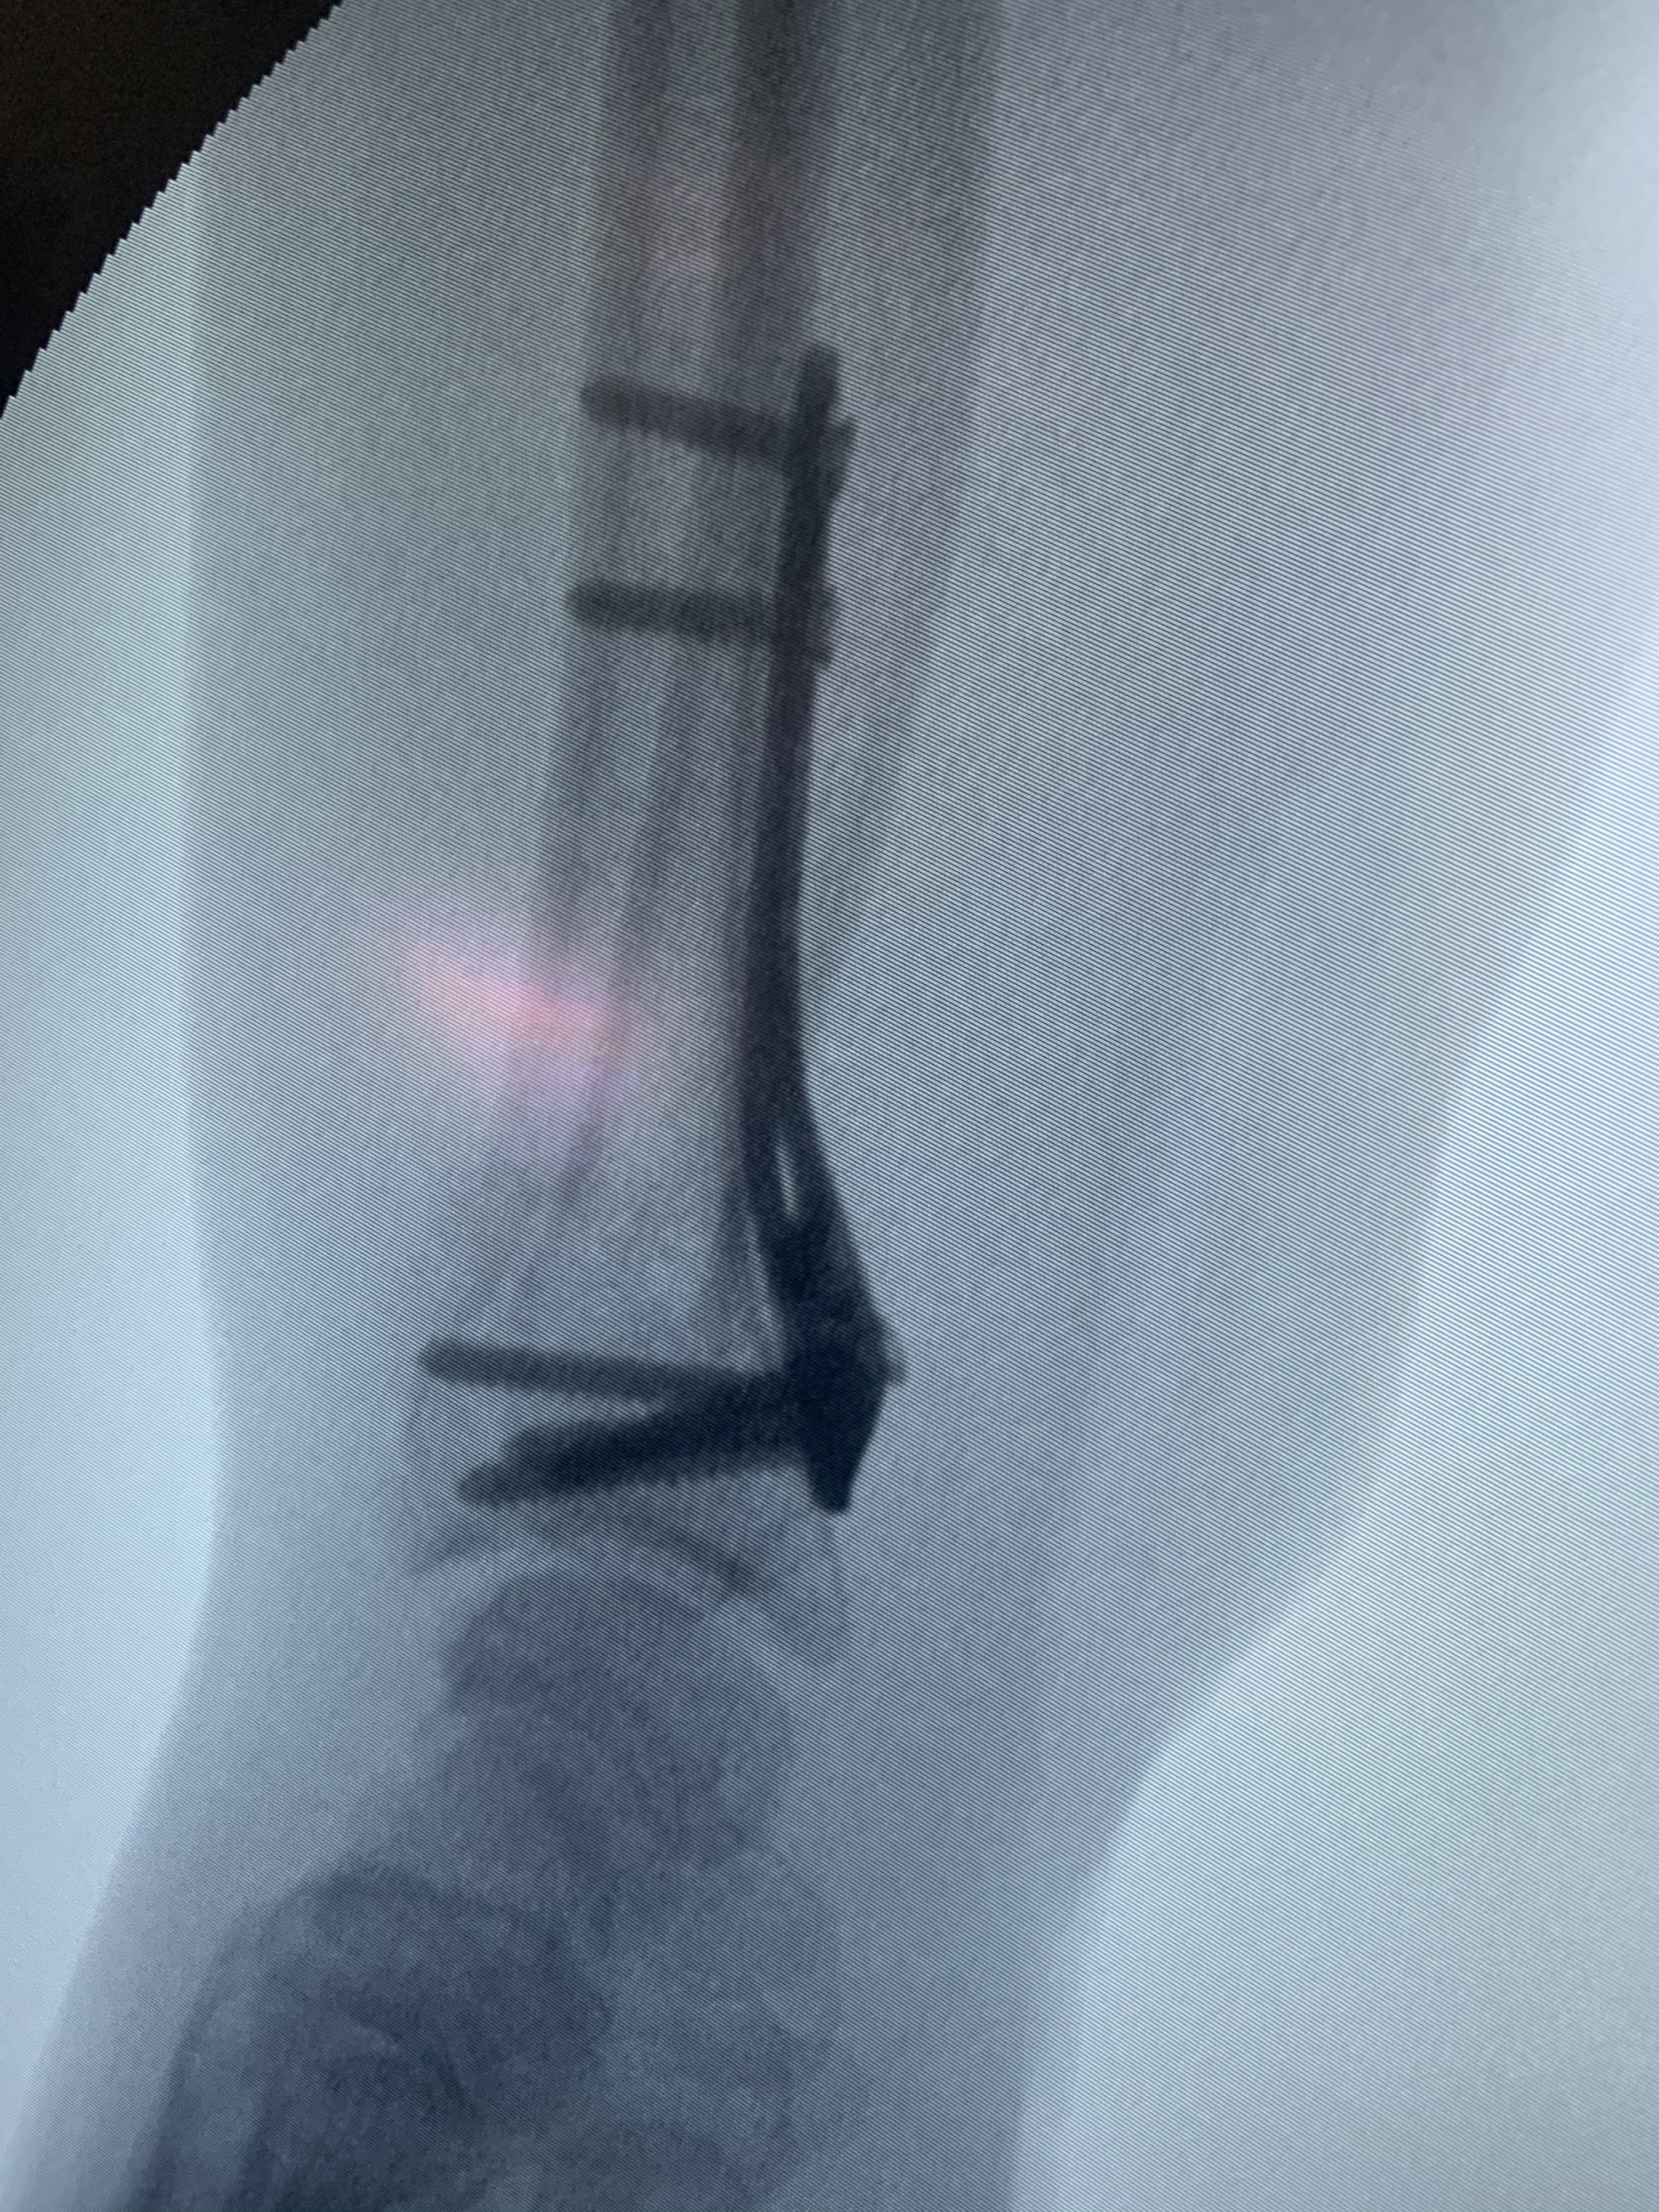

Galería de fotos clínica, servicios, cirugías, casos de pacientes Visítenos, ambiente limpio, agradable y seguro. Trabajando Operando en tiempos de coronavirus Dr Barquero Traumatologo Compartir en X (Se abre en una ventana nueva) X Comparte en Facebook (Se abre en una ventana nueva) Facebook Imprimir (Se abre en una ventana nueva) Imprimir Compartir en WhatsApp (Se abre en una ventana nueva) WhatsApp Enviar un enlace a un amigo por correo electrónico (Se abre en una ventana nueva) Correo electrónico Me gusta Cargando...